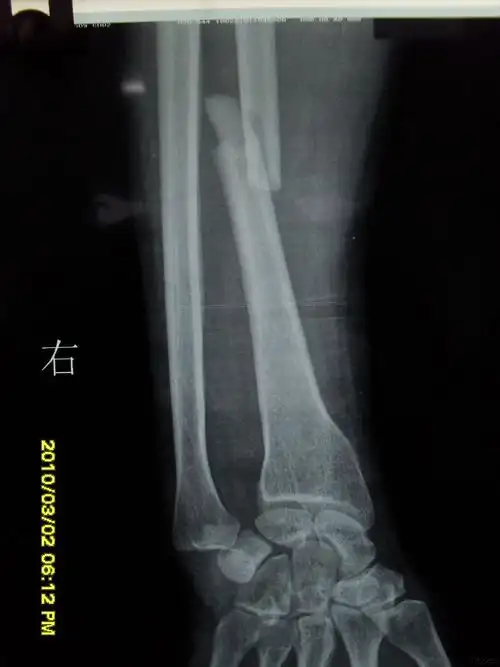

sauvékapandji术治疗陈旧性下尺桡关节掌侧脱位1例报告并文献复习